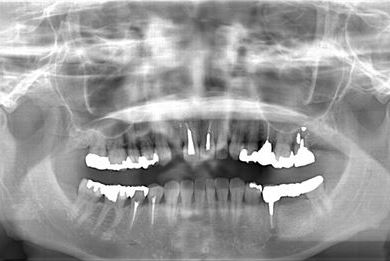

インプラントの症例写真 IMPLANT

骨再生スピードインプラント治療+セラミック治療

| 治療方針 | 上前歯の欠損部分は、ブロック骨移植により、インプラント治療を可能にする。左下奥の欠損部分は、保存不可能な歯を抜歯すると同時にインプラントを埋入し、治療期間を短縮する。 | ||||||||||||||||||||||||||||||||

| 治療内容 | インプラント3本(抜歯即日スピードインプラント、骨移植)、メタルボンドセラミッククラウン5本(メタルボンド用土台1本)、オールセラミッククラウン1本(オールセラミック用土台1本) | ||||||||||||||||||||||||||||||||